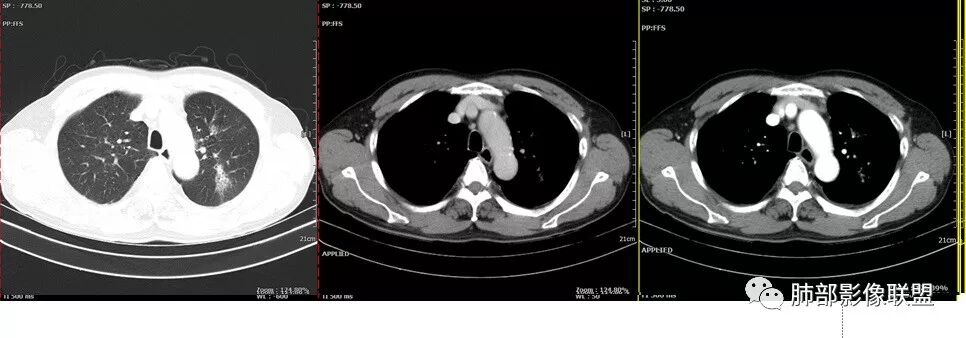

胸CT:左肺上叶前段实变,其周围及左肺上叶尖后段可见肺气肿背景下渗出性病变,病灶内可见支气管扩张,气道壁呈不规则增厚,双肺散在小结节状影;右肺下叶结节影,内可见空泡,边缘模糊,不规则。增强可见病灶内血管造影征,右肺门增大,纵隔淋巴结多发肿大。

左肺上叶大片混合网格磨玻璃影,边界清,边缘分叶膨隆,内支气管走行狭窄扩张,实变区边界清,上叶支气管管腔窄,心膈角淋巴结肿大,考虑肺炎型肺癌—腺癌。左肺下肺门结节,边缘膨隆,突入中间段及下叶支气管腔,背段支气管阻塞,周围少量小花小草,考虑鳞癌。右下叶外侧基底段结节,边缘有膨隆,有血管牵拉进入,上缘支气管贴边,考虑肺癌,性质?

薏米:老年男性,发热,咳嗽5天,胸痛2天,平素慢性咳嗽,咳痰10年,未系统诊治,基础糖尿病史,此次以急性发病为主,白细胞正常,CRP增高,IGE增高,CEA轻度增高,左肺上叶散在片状密度增高影,边界清楚,小叶间隔增厚,内有磨玻璃影,部分支气管壁增厚,部分有扩张,部分有近段粗细不均,少许气囊,右肺下叶可见一结节影,有凹陷,有膨隆,似有结节感,综合考虑左肺上叶考虑黏液性腺癌,鉴别曲霉,抗感染后复查:右肺下叶恶性。

老年男性,糖尿病病史,crp及ige明显增高,cea轻度增高。影像:左肺上叶前段网格状高密度影,部分实变,部分前段支气管走形僵直。右肺下叶背段近肺门处及右肺下叶外侧基底段各见一枚结节,可见浅分叶,外侧基底段结节可见空泡。纵隔多发淋巴结肿大。综合考虑:肺癌,粘液腺癌?

患者中老年男性,发热,咳嗽5天,胸痛2天。慢性咳嗽,咳痰10余年,目前出现活动后胸闷气短,有基础糖尿病、高血压病史,查白细胞正常,CRP增高,IGE增高,CEA轻度增高。胸部CT:左肺上叶片状密度增高影,边界清楚,内血管穿行,呈蜂窝网格状,内有磨玻璃影,部分支气管壁增厚,部分有扩张,部分有近段粗细不均;右肺下叶可见一结节影,有凹陷,有膨隆,似有结节感,右侧肺门淋巴结肿大,纵隔多发淋巴结肿大、部分伴有钙化。综合考虑恶性病变,左上肺粘液腺癌可能,右下肺小细胞癌?两源论考虑:左上肺粘液腺癌或粘膜相关性淋巴瘤?右下肺结核球伴肺门淋巴结肿。

老年男性,急性病史,咳嗽咳痰伴胸疼入院。血象不高,但crp升高,ige明显升高,肿瘤标志物cea稍高一点,左肺上叶磨玻璃实变影,似有地图征,边缘模糊,支气管血管走行自然,支气管扩张,纵隔淋巴结肿大并钙化,右肺下叶肺门处小结节,边缘光滑。考虑良性病变,结节病?淀粉样变?鉴别肺癌:粘液腺是胸膜下外围分布,这个感觉是沿支气管血管束分布。